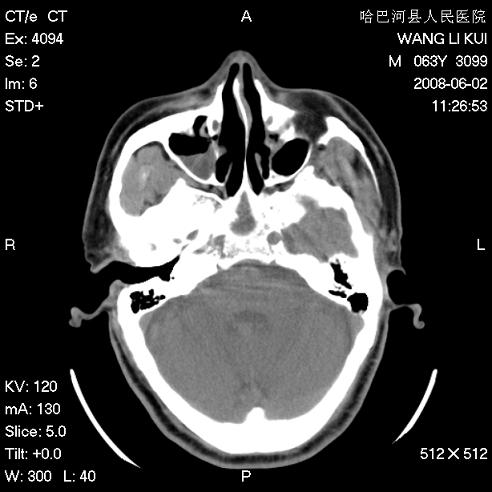

标题: CT13803:反复性鼻塞、流涕一年余 [打印本页]

标题: CT13803:反复性鼻塞、流涕一年余

副鼻窦炎,右上额窦积脓。左眼肌锥内见致密影,视神經受压

1.全组副鼻窦炎2.双侧上颌窦积液

1)全副鼻窦炎(左侧上颌窦黏膜下囊肿或息肉)。2)左眼眶肌锥内不规则小结节状软组织密度影;考虑为小血管瘤可能。建议行ct增强扫描检查。

全组副鼻窦炎,左侧肌锥内不规则形软组织肿块影,与眼外肌密度相当,左侧视神经受压,肿块与视神经及眼外肌分界清晰,眼外肌无增粗,眶壁无破坏,球后脂肪间隙不模糊,考虑良性改变,小血管瘤或神经源性肿瘤可能,建议增强扫描。

谢谢,增强扫描做了,眶内病灶与海绵窦同步明显强化,血管瘤